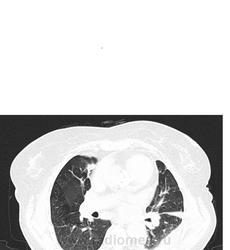

Мне видится хроническая ТЭЛА-упорно зрю мозаичность, видится сумасшедшая легочная гипертензия, застойные сердечные дела, и о ужас... мерещится мезотелиома... все эти узелки по плевре, каплевидны формы, прям по междолевочке... да и шарик в печени - али не гиповаскулярный метастаз???

ТЭЛА без контраста не исключишь. При таком гидротораксе добавил бы исследование на животе (или на боку, если ей это легче). Кстати, а почему сразу мезотелиома? А в легких застой и отек.

мезотелиома злокачественная сопровождается рецидивирующим большим гидротораксом, а доброкачественный вариант выглядит не так . Тут мне видится междолевой и костальный плеврофиброз , осумкавание жидкости по заднебоковой поверхности , возможно. На счет легких согласна с предыдущим мнением, хотя на счет отека у меня не повернулся бы язык.

- смотрим на центральные сосуды - есть ли признки легочной гипертензии - косвенные признак, но если есть мозаичная перфузия + легочная гипертензия - высока вероятность ХТЛГ (КТ-признаки ЛГ: увеличение диаметра ветвей легочной артерии >28-29 мм. Увеличение калибра сегментарных легочных артерий больше соотношения 1:1 в 3-х и более долях. Увеличение диаметра ствола легочной артерии > восходящей аорты. Если делать с кардиосинхронизацией - то можно использовать формулу расчета коэфициента растяжимости легочнйо артерии - если он меньше 16,5 - то можно ставить ЛГ (этот коэфициент напрямую коррелирует с давлением в легочой артерии); кроме того существуют "сердечные" признаки постановки ЛГ и

По поводу сосудистой гиперволемии и интерстициального отека - он может выгледеть в виде матового стекла, но будет располгаться в гравитационно-зависимых зонах (то есть в задних отделах различных долей легких: паракостально, по ходу междолевых щелей), часто если есть гиперволемия то видно относительное расширение легочных сосудов - преимущественно за счет легочных вен и наличие ретикулярного паттрена - утолщение периферического субплеврального и междолькового интерсиция. Чтобы отличить воспалительыне изменения в задних субплевральных отделах от застойных - можно повернуть на живот. Но, по большому счету, делать этого не надо,

В вышеприведенном случае - явных КТ-данных за наличие отек - я не вижу.

По поводу жидкостных образований паракостально слева - на мой взгляд просто осумкование жидкости (но кто его точно знает...) Мехотелиома не исключена.

Вообщим на мой взгляд - ХТЛГ возможно рецидив.

-Легочный ствол - 49мм

- правая ЛА 35мм

- левая ЛА 31мм

- дистальный сегмент восх.АО - 38мм

- проксимальный сегмент нисх. АО- 29мм

- дистальный сегмент нисх.АО - 28 мм